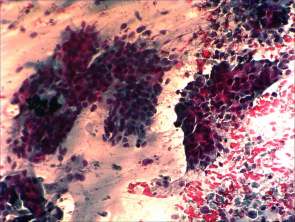

Cytological picture. There was no colloid in the background. Hyperchromatic epithelial columnar cells were found with clear cytoplasm. They were in irregular cell groups with loss of polarity and nuclear crowding.

Cytological diagnosis: a pattern corresponding to metastasis of the urinary bladder cancer.